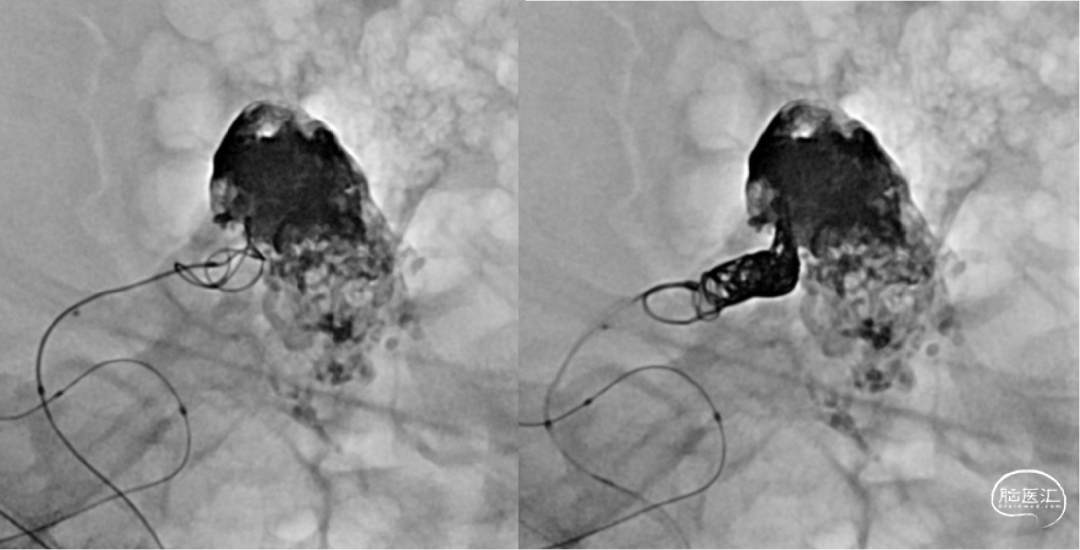

经Echlon10微导管填入弹簧圈做塞子

经Apllo微导管注入Onyx胶

术后造影脑动静脉畸形消失